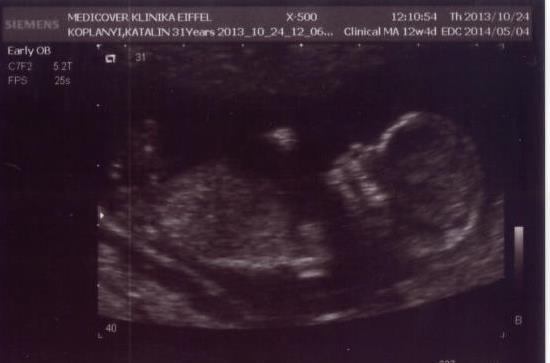

ez a Medicover Egészségközpontban volt, az Eiffel téren, ott végzik nekem teljesen a terhesgondozást. Egy helyen minden szakág megtalálható, így csak oda járok végig, a labor is ott van.

Amúgy ha valaki magán UH-ra menne, és nincs ötlete, nagyon tudom őket ajánlani, mert összehasonlíthatatlanul jók a gépek azokhoz képest, ahol eddig jártam, pedig azok is magánorvosok voltak.

Amúgy az a vicc, hogy a mai UH szerint 12+4 naposnak számítok (ami azért +/- pár nap mindig lehet), és az Istenhegyire okt. 30-ra adtak időpontot, amikor is már elmúltam volna 13 hetes...

Szóval tök jó időpontban voltam a kombinált teszten.![]()